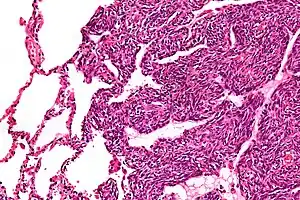

| Micrograph of a monophasic synovial sarcoma. The histologic appearance is non-specific and overlaps with MPNST and fibrosarcoma. H&E stain. | |

Two cell types can be seen microscopically in synovial sarcoma. One fibrous type, known as a spindle or sarcomatous cell, is relatively small and uniform, and found in sheets. The other is epithelial in appearance. Classical synovial sarcoma has a biphasic appearance with both types present. Synovial sarcoma can also appear to be poorly differentiated or to be monophasic fibrous, consisting only of sheets of spindle cells. Some authorities[3] state that, extremely rarely, there can be a monophasic epithelial form which causes difficulty in differential diagnosis. Depending on the site, there is similarity to biphenotypic sinonasal sarcoma, although the genetic findings are distinctive.